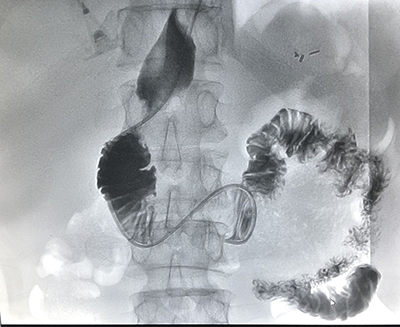

吉林省腫瘤醫(yī)院介入中心建筑面積2200平方米,開放床位35張。擁有UNIQ FD20C 血管造影機?,F(xiàn)有主任醫(yī)師1名,副主任醫(yī)師1名,主治醫(yī)師2名,醫(yī)師2名。(其中博士1名,碩士4名)??剖易?992年開展腫瘤介入微創(chuàng)的診療工作,30年以來,開展了肝癌、肺癌、肝轉(zhuǎn)移癌、肺轉(zhuǎn)移癌、膽管癌、消化道腫瘤、泌尿系統(tǒng)腫瘤、骨轉(zhuǎn)移瘤、盆腔腫瘤等各種良、惡性腫瘤的微創(chuàng)介入手術(shù)2萬余例(包括腫瘤動脈灌注化療栓塞術(shù)、微波消融術(shù)和125I放射粒子植入術(shù)(病種包括:肝癌、肝轉(zhuǎn)移癌、肺癌、肺轉(zhuǎn)移癌、骨轉(zhuǎn)移癌、腎上腺轉(zhuǎn)移癌等)、子宮肌瘤及肌腺癥栓塞術(shù)、經(jīng)皮穿刺骨水泥注射椎體成形術(shù)、食管、膽管狹窄支架置入術(shù)、各部位腫瘤急性出血的栓塞止血術(shù)、胃腸營養(yǎng)管、腸梗阻導(dǎo)管植入術(shù)等)。在國內(nèi)外首先提出低功率消融的治療理念,經(jīng)過1000余例臨床手術(shù)證實,療效確切,無并發(fā)癥,得到了國內(nèi)外同行的廣泛認(rèn)可,并在全國逐步推廣。2011年在國內(nèi)外率先開展三氧化二砷聯(lián)合局部微創(chuàng)介入治療中晚期肝癌的隨機對照研究,提出了早期全身干預(yù)與局部治療的序貫療法,取得了明顯的成績,經(jīng)過中位60個月隨訪期,治療組明顯優(yōu)于常規(guī)對照組,中晚期肝癌的5年生存期達到38.2%,達到了國際領(lǐng)先水平。在國內(nèi)率先開展了多項靶向藥及免疫治療聯(lián)合介入微創(chuàng)治療肝癌、肺癌等臨床研究,取得了較好的成績。在科研方面,共發(fā)表SCI及核心期刊論文100余篇;2019年度獲吉林省科技進步二等獎1項,吉林省科技進步三等獎1項,2014年獲長春市科技進步二等獎1項??剖覟榧质】拱﹨f(xié)會介入治療專業(yè)委員會主委單位,主辦國家級及省級學(xué)術(shù)會議10余次。

(介入術(shù)中操作)(肝癌的介入治療)